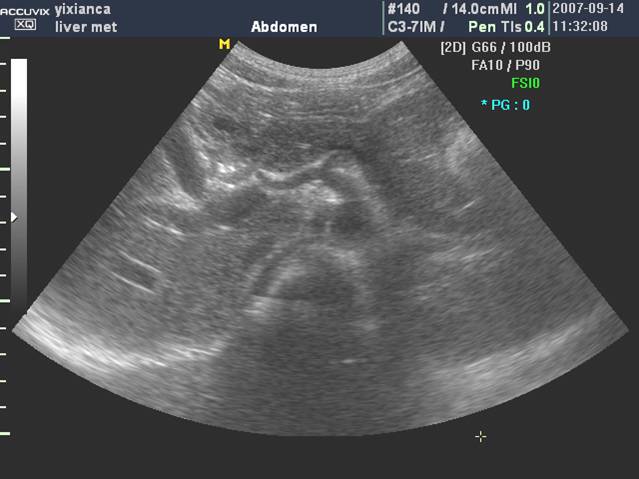

(二)通过肝静脉进行分叶

肝静脉主干在叶间裂或段间裂内行走,易于超声显示,最便于进行肝脏分叶、分段。

1. 肝右静脉行走于右叶间裂内-右前、后叶分界

2. 肝中静脉行走于正中裂的后半部和尾状叶内,右半肝与左半肝分界

3. 肝左静脉近端走行左叶间裂内-左内外叶分界

4. 肝左静脉远端位于左段间裂内-为左外叶上段和下段分界

肝左右叶的超声分界标志(肝中静脉)

肝左右叶的超声分界标志(胆囊切迹-下腔静脉左缘连线)

肝左内外叶的超声分界(肝圆韧带-门静脉左支矢状部-静脉韧带)

肝左外叶上下段的超声分界

肝右叶上下段的超声分界